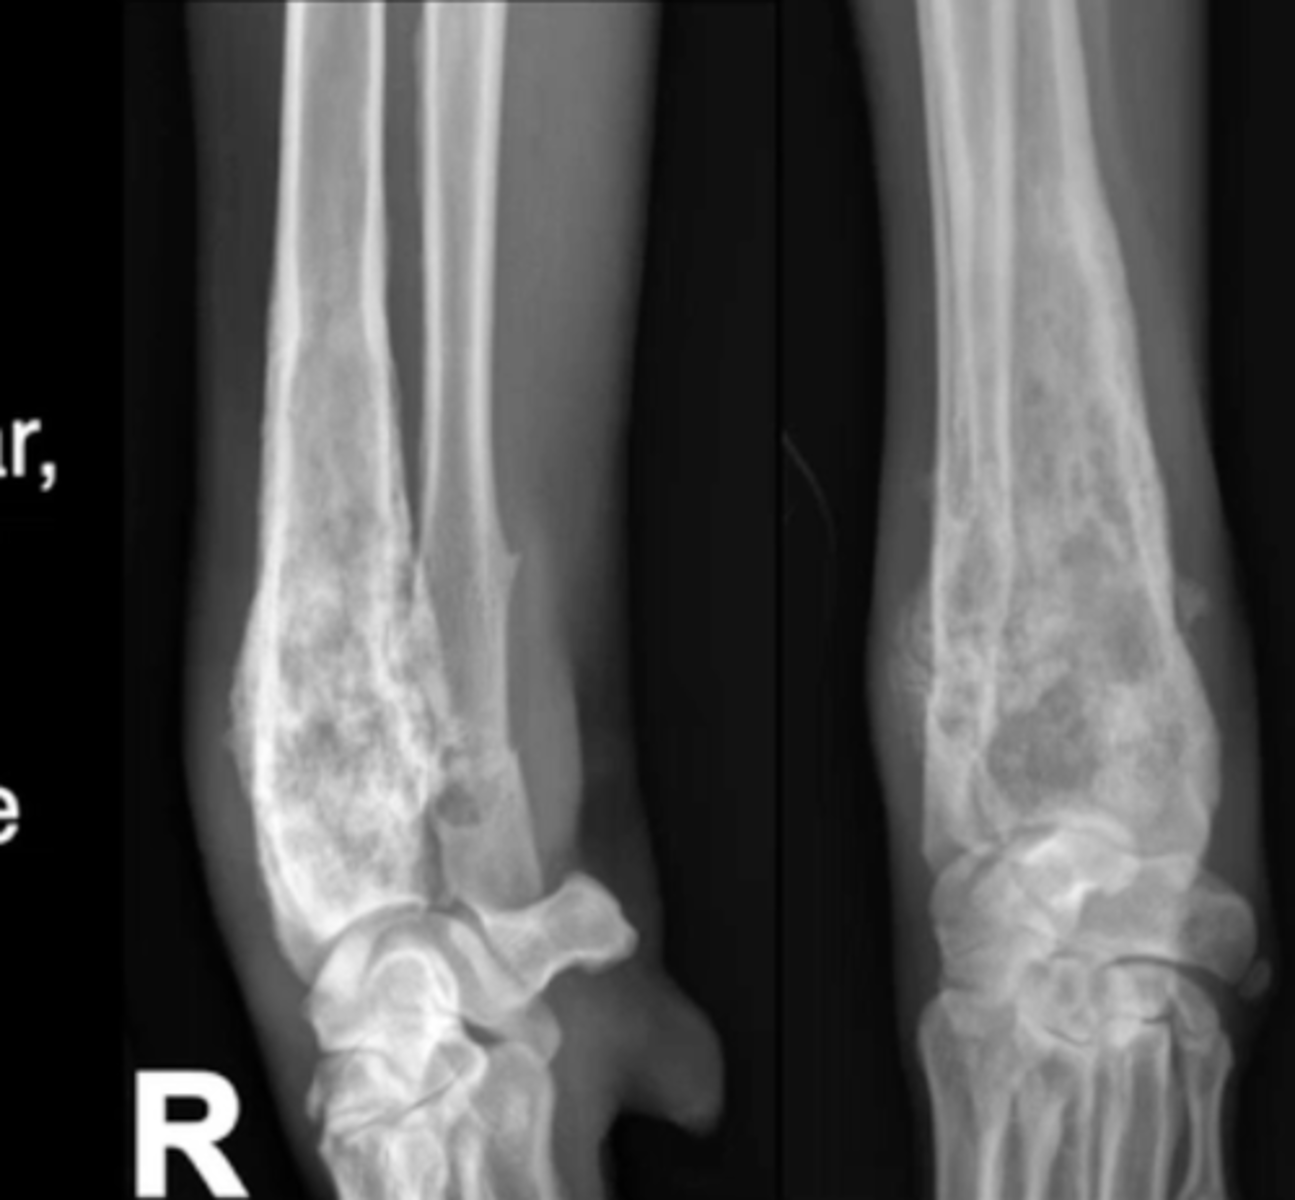

moth eaten

Which pattern of destruction is this?